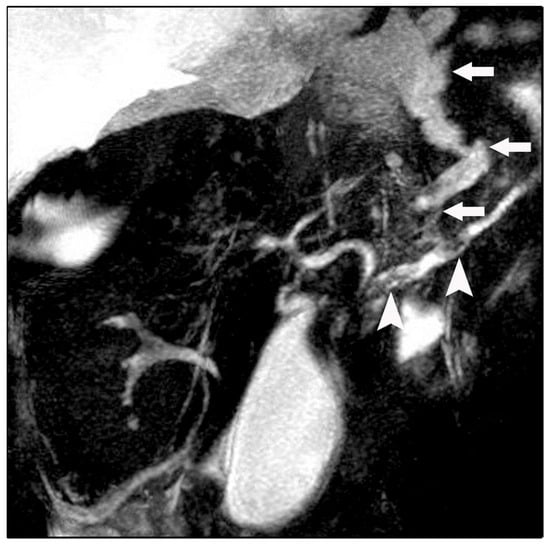

Figure 3.

Magnetic resonance cholangiopancreatography (MRCP) revealing a fistulous fluid tract arising from a disruption of the main pancreatic duct and coursing toward the esophageal hiatus (arrows). Intraductal filling defects consistent with pancreatic duct calculi are also noted (arrowheads).